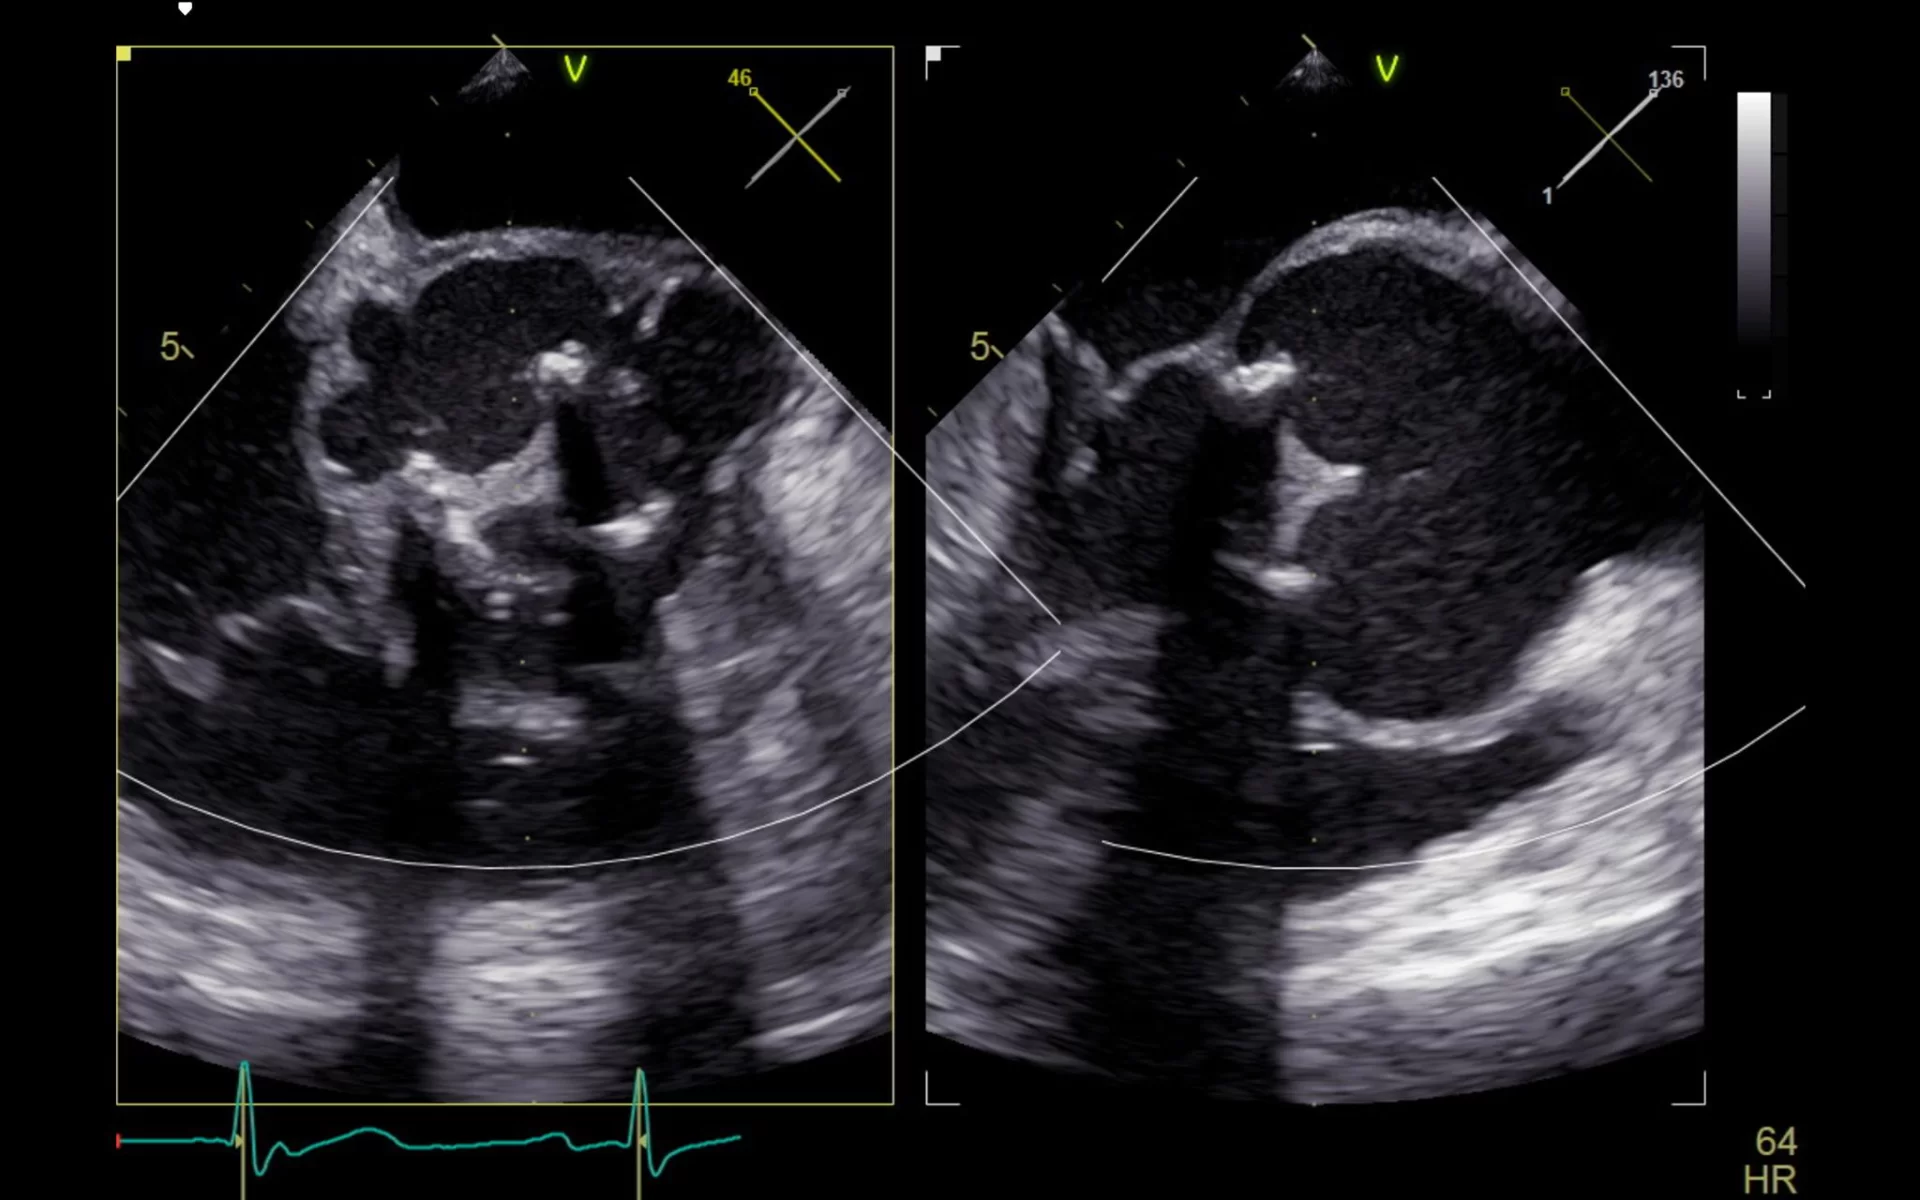

Η αορτική βαλβίδα είναι μία από τις τέσσερις βασικές καρδιακές βαλβίδες και βρίσκεται ανάμεσα στην αριστερή κοιλία της καρδιάς και την αορτή, τη μεγαλύτερη αρτηρία του σώματος. Ο ρόλος της είναι να επιτρέπει τη ροή του αίματος από την καρδιά προς το υπόλοιπο σώμα, εμποδίζοντας την επιστροφή του αίματος προς τα πίσω. Πρόκειται για μια «μονόδρομη» βαλβίδα που ανοίγει και κλείνει συγχρονισμένα με τον καρδιακό παλμό, εξασφαλίζοντας την ομαλή κυκλοφορία του αίματος.

- Αορτική στένωση: Πρόκειται για στένωση του ανοίγματος της βαλβίδας, με αποτέλεσμα να εμποδίζεται η ροή του αίματος από την καρδιά προς την αορτή. Συνήθως προκαλείται από εκφύλιση λόγω ηλικίας, αλλά μπορεί να είναι και συγγενής ή αποτέλεσμα ρευματικού πυρετού.

- Αορτική ανεπάρκεια: Συμβαίνει όταν η βαλβίδα δεν κλείνει σωστά, με αποτέλεσμα το αίμα να επιστρέφει πίσω στην καρδιά μετά τη συστολή. Αυτό οδηγεί σε επιβάρυνση της καρδιάς και σταδιακή καρδιακή ανεπάρκεια.

- Αντικατάσταση αορτικής βαλβίδας: Η πιο κοινή προσέγγιση, όπου η παθολογική βαλβίδα αντικαθίσταται με μηχανική ή βιολογική πρόθεση. Μπορεί να γίνει με κλασικό χειρουργείο (ανοιχτή καρδιοχειρουργική) ή με ελάχιστα επεμβατικές τεχνικές.

- Διακαθετηριακή εμφύτευση αορτικής βαλβίδας (TAVI): Μια λιγότερο επεμβατική τεχνική για ασθενείς υψηλού κινδύνου, όπου η νέα βαλβίδα τοποθετείται μέσω καθετήρα, συνήθως από τη μηριαία αρτηρία.